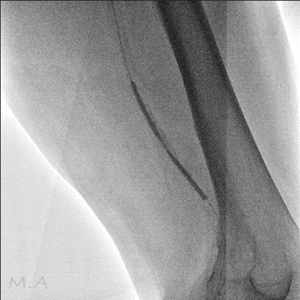

血管撮影装置

当院は令和6年3月の新病院発足に伴い、より高精度で安全な検査・血管内治療(IVR:Interventional Radiology)を提供するため最新の島津製作所製バイプレーンシステムTrinias B12s(Opera smart)を導入しました。

平面型X線検出器(FPD:Flat Panel Detector)を搭載し、カテーテルを用いた高度な血管内治療においてより少ないX線で高い解像度の画像を描出可能となりました。

バイプレーンシステムを採用したことにより、一回の造影剤注入で2方向撮影が可能となり、従来のシングルプレーンと比較して造影剤使用量を半分程度に抑えることができ、被ばくを低減すると共に検査時間の短縮にも繋がり、より患者さまの負担を軽減することが可能となりました。

冠動脈造影検査(CAG:Coronary Angiography)をはじめ、経皮的冠動脈インターベンション(PCI:Percutaneous Coronary Intervention)、下肢動脈のインターベンション(EVT:Endovascular Treatment)、肝動脈化学塞栓術(TACE:Transcatheter Arterial Chemo-Embolization)等、心血管領域、腹部血管領域における高度なカテーテル治療においてその性能を発揮しております。